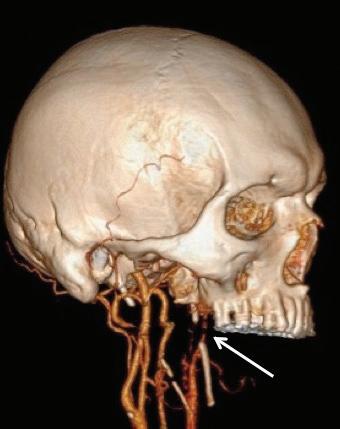

Eagle syndrome: Transient ischemic attack and subsequent carotid dissection

A 62-year-old man initially presented to our institution 3 months before his final diagnosis with transient right-sided weakness and brief loss of consciousness after reaching across his body in the shower. His medical history was significant for hypertrophic cardiomyopathy and atrial fibrillation. He had an implantable cardiac device and was on lifelong anticoagulation. Head computed tomography (CT) and CT angiography (CTA) were unremarkable, and although a transient ischemic attack (TIA) was thought to be unlikely given the anticoagulation therapy, this was a working diagnosis based on his symptoms, which were otherwise unexplained, and he was sent home.

The patient returned 3 months later with sudden-onset behavioral changes, disorganized speech, and right-sided weakness. He reported no specific activity related to symptoms. CTA demonstrated complete left internal carotid occlusion at the level of the styloid tip, 1-cm cranial to the bifurcation, which extended to the carotid terminus (figure 1). Review of imaging obtained at his presentation 3 months earlier demonstrated a normal carotid.

CT of the head obtained at the most recent visit demonstrated new anterior, middle, and posterior circulation infarcts. In addition, we observed not only that his left styloid process was elongated (3.0 cm), but also that his stylohyoid ligament was calcified to the hyoid and possibly fractured (figure 2). We speculate that the fracture might have acted as a lead-point, causing injury

and subsequent dissection of the patient’s carotid. The contralateral styloid process was within normal limits, but the ligament was also calcified.

Prophylactic contralateral styloidectomy was considered, but the patient was deemed a poor surgical candidate given his underlying cardiomyopathy and anticoagulation. After further review of imaging, we felt his right carotid was a safe distance from the right styloid and ligament. As the left carotid was occluded to the skull base, he was not offered revascularization. We speculate that our patient’s initial presentation

A B

Figure 1. A: 3-D reconstruction of the patient’s CTA with soft-tissue subtraction demonstrates the elongated and calcified stylohyoid ligament and dissected carotid artery cranial to the ligament (arrow). B: Additional 3-D reconstruction of the CTA with bone and soft tissue removed further demonstrates the dissected left internal carotid artery (arrow).

might have been a harbinger of his impending cerebrovascular accident.

Eagle Syndrome is an uncommon but well-described entity with a nonspecific clinical presentation; more benign manifestations include globus sensation, dysphagia, facial neuralgias, throat pain, and cranial neuropathies, for which a differential is extensive.1,2 In the presence of an elongated styloid bone or stylohyoid, diagnostic consideration is often given to Eagle syndrome, but it may have a more insidious presentation. Elongation of the styloid also has been reported as a cause for symptomatic carotid disease, including TIA, Horner syndrome, eye pain, and cluster headache.3 Dissection associated with elongated styloids has been reported in the neurology literature,4 but to the best of our knowledge, no prior reports have demonstrated TIA with a normal carotid and subsequent carotid dissection during two separate clinical presentations.